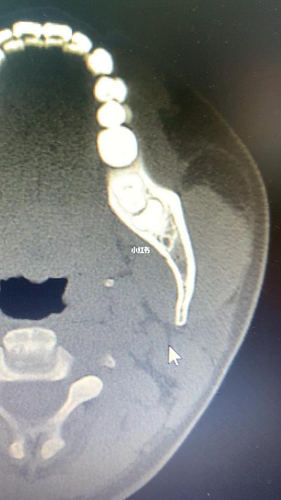

拔智齿究竟是否需要拍ct,这个应根据具体情况来决定的,一般情况下,可以先拍个全景牙片,因为全景牙片就已经可以大概看到牙根的生长方向和牙齿的生长趋势,但如果智齿比较靠近下颌神经管或者是在神经管里面,则需要拍ct来观察清楚规避风险,建议需要拔智齿的人最好听从医生的安排,配合治疗。